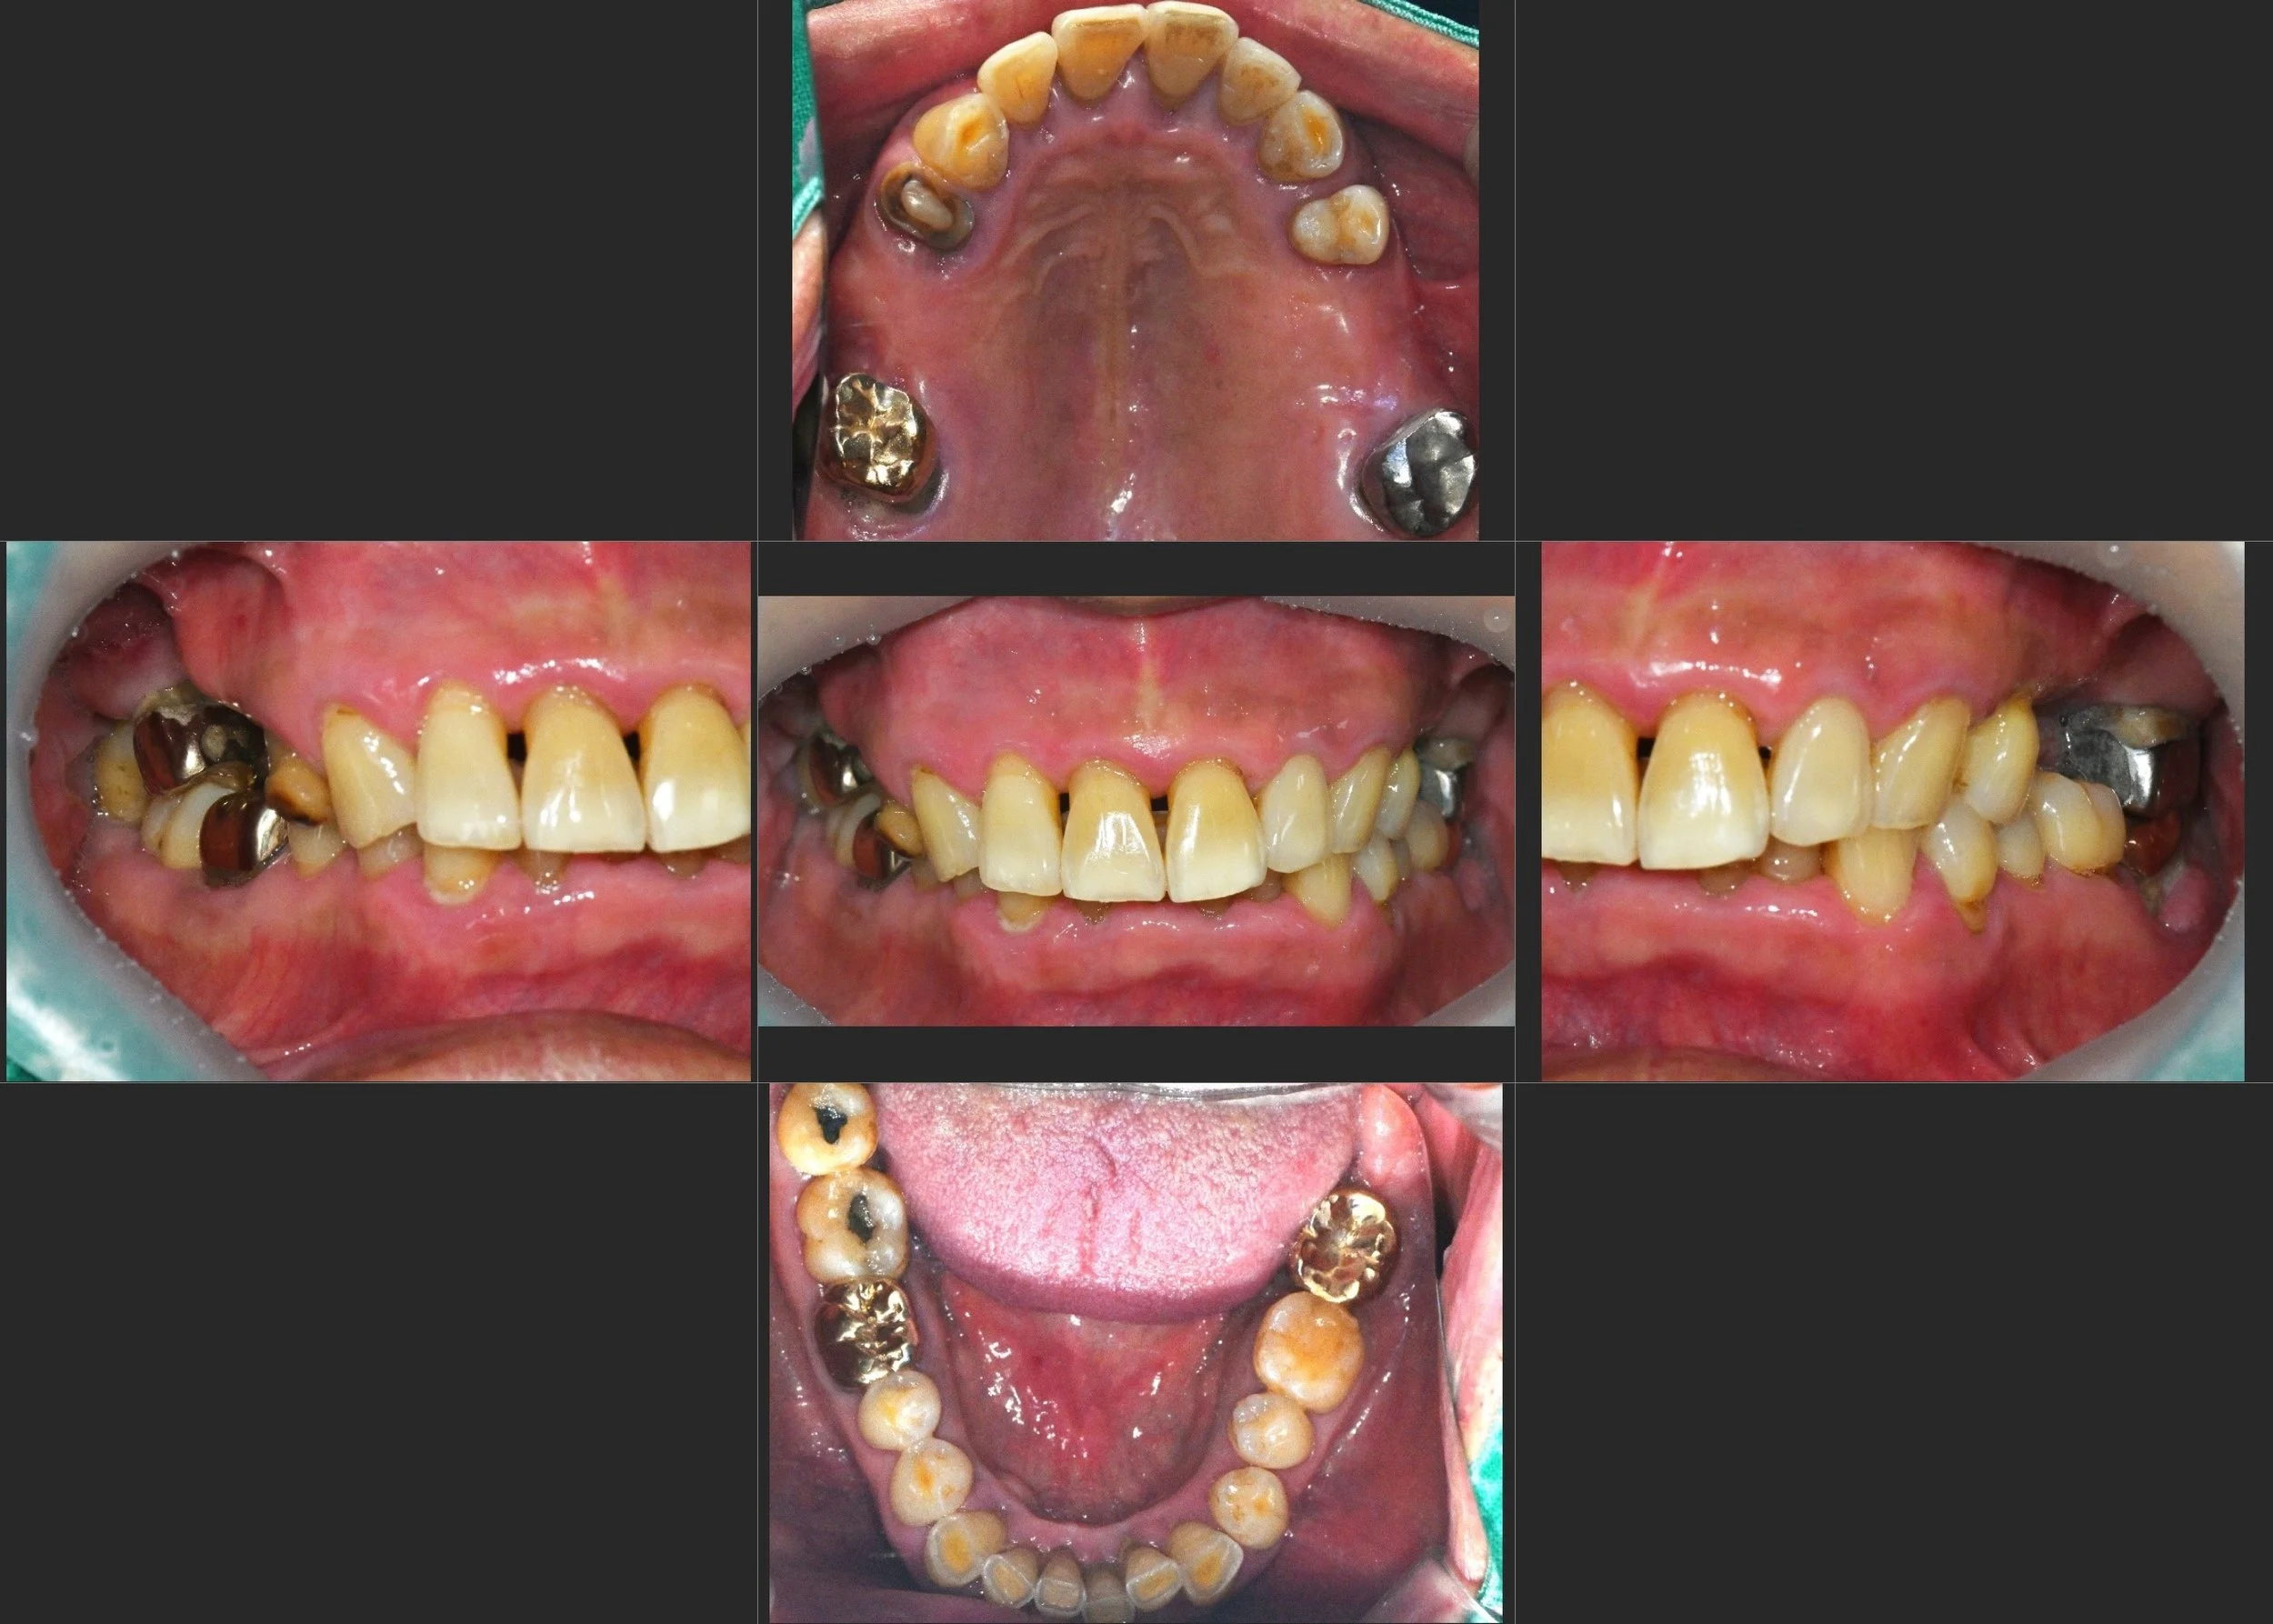

The patient presented with a severely collapsed occlusion, resulting in marked mandibular retrusion

and an excessive overjet.

Advanced anterior tooth wear and fractures were evident, caused by prolonged overload and unstable occlusal contacts.

INTRA ORAL - BEFORE